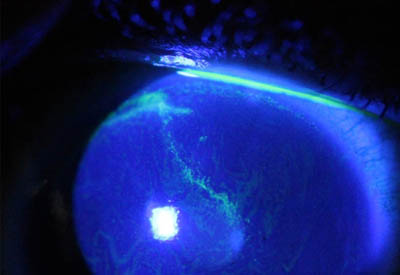

Formación de lineas epiteliales elevadas que pueden dar la imagen de Seudodendrítas

Formación de lineas epiteliales elevadas que pueden dar la imagen de Seudodendrítas + Perineuritis

No tienen los bulbos terminales de las dendritas del Herpes Simple

Dendritas Herpéticas